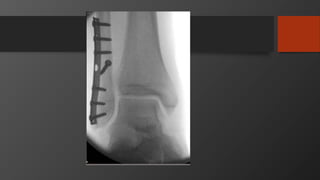

Treatment

• Non-operative

• Minimally displaced frx (˂ 3 mm)

• Hinged knee brace + immediate passive ROM

• Operative

• Delayed ORIF and temporary external fixator

• Significant soft tissue injury

• ORIF

• Displaced ˃ 3 mm

• All bicondylar fracture

• All medial plateau fractures